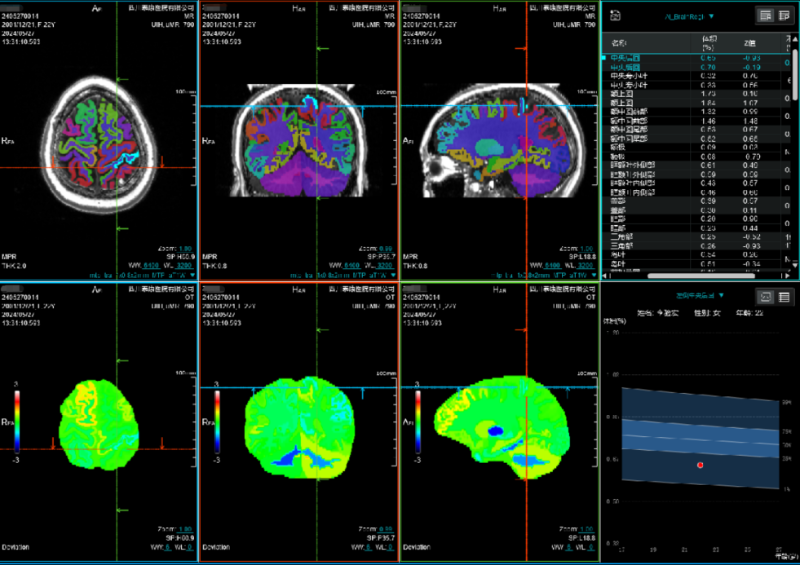

入院后,医院为她进行了详尽的颅脑MRI增强及头颅CT薄扫检查,结果显示其病变位于左侧顶上小叶,病变对脑组织压迫明显(病变周围脑组织CBF灌注明显降低、较对侧脑回体积明显减小),且与左侧大脑上静脉紧密相关,动态视频脑电图分析进一步提示病灶周围脑组织存在异常放电。

术前MRI轴位图像

术前MRI冠状位图像

术前MRI矢状位图像

术前ASL图像(显示病变周围脑组织灌注降低)

术前MRI提示左侧中央后回较对侧稍小。